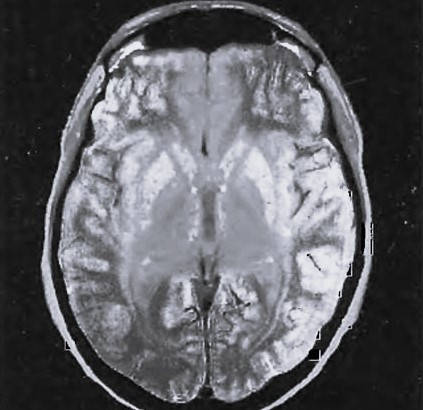

Затемнение на мрт

Затемнение на мрт 140 фото